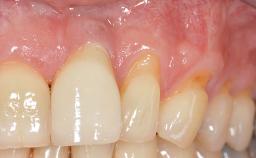

Early Implant Placement, Contour Augmentation, and Autologous Connective-Tissue Graft Using a Tunneling Technique to Replace an Upper Incisor with Generalized Gingival Recession

Variations in soft-tissue volume, evidenced either by an overabundance (Evian and coworkers 1993; Levine and McGuire1997; Dolt and Robbins 1997) or by a deficiency of soft or hard tissue can complicate implant-supported rehabilitations in the esthetic zone (Lorenzana 2008; Lorenzana and coworkers 2009). The present case illustrates the replacement of a failing upper left lateral incisor complicated by generalized severe gingival recession in the esthetic zone.